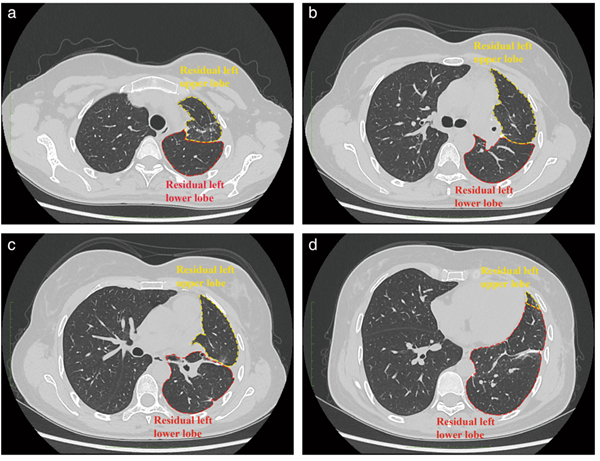

△術(shù)后3個月的胸部高分辨率計算機斷層掃描(CT)顯示,患者的左肺沒有結(jié)節(jié)殘留。

在手術(shù)過程中,醫(yī)生在仿真模型的指導下成功定位了結(jié)節(jié)。所有12個結(jié)節(jié)都被切除,其中9個結(jié)節(jié)被發(fā)現(xiàn)并標記為病理檢查,其余3個結(jié)節(jié)由于體積小而沒有被目測解剖。最大的結(jié)節(jié)11被病理診斷為微侵襲性腺癌(MIA)。研究人員對相關(guān)的淋巴結(jié)進行了取樣,并在病理上確認了無腫瘤。整個手術(shù)時間為200分鐘,12個結(jié)節(jié)定位只需要15分鐘,即平均每個結(jié)節(jié)1.25分鐘?;颊咝g(shù)后5天拔除胸管,順利康復。術(shù)后3個月進行了HRCT檢查,檢驗證明左肺沒有殘留的結(jié)節(jié)。